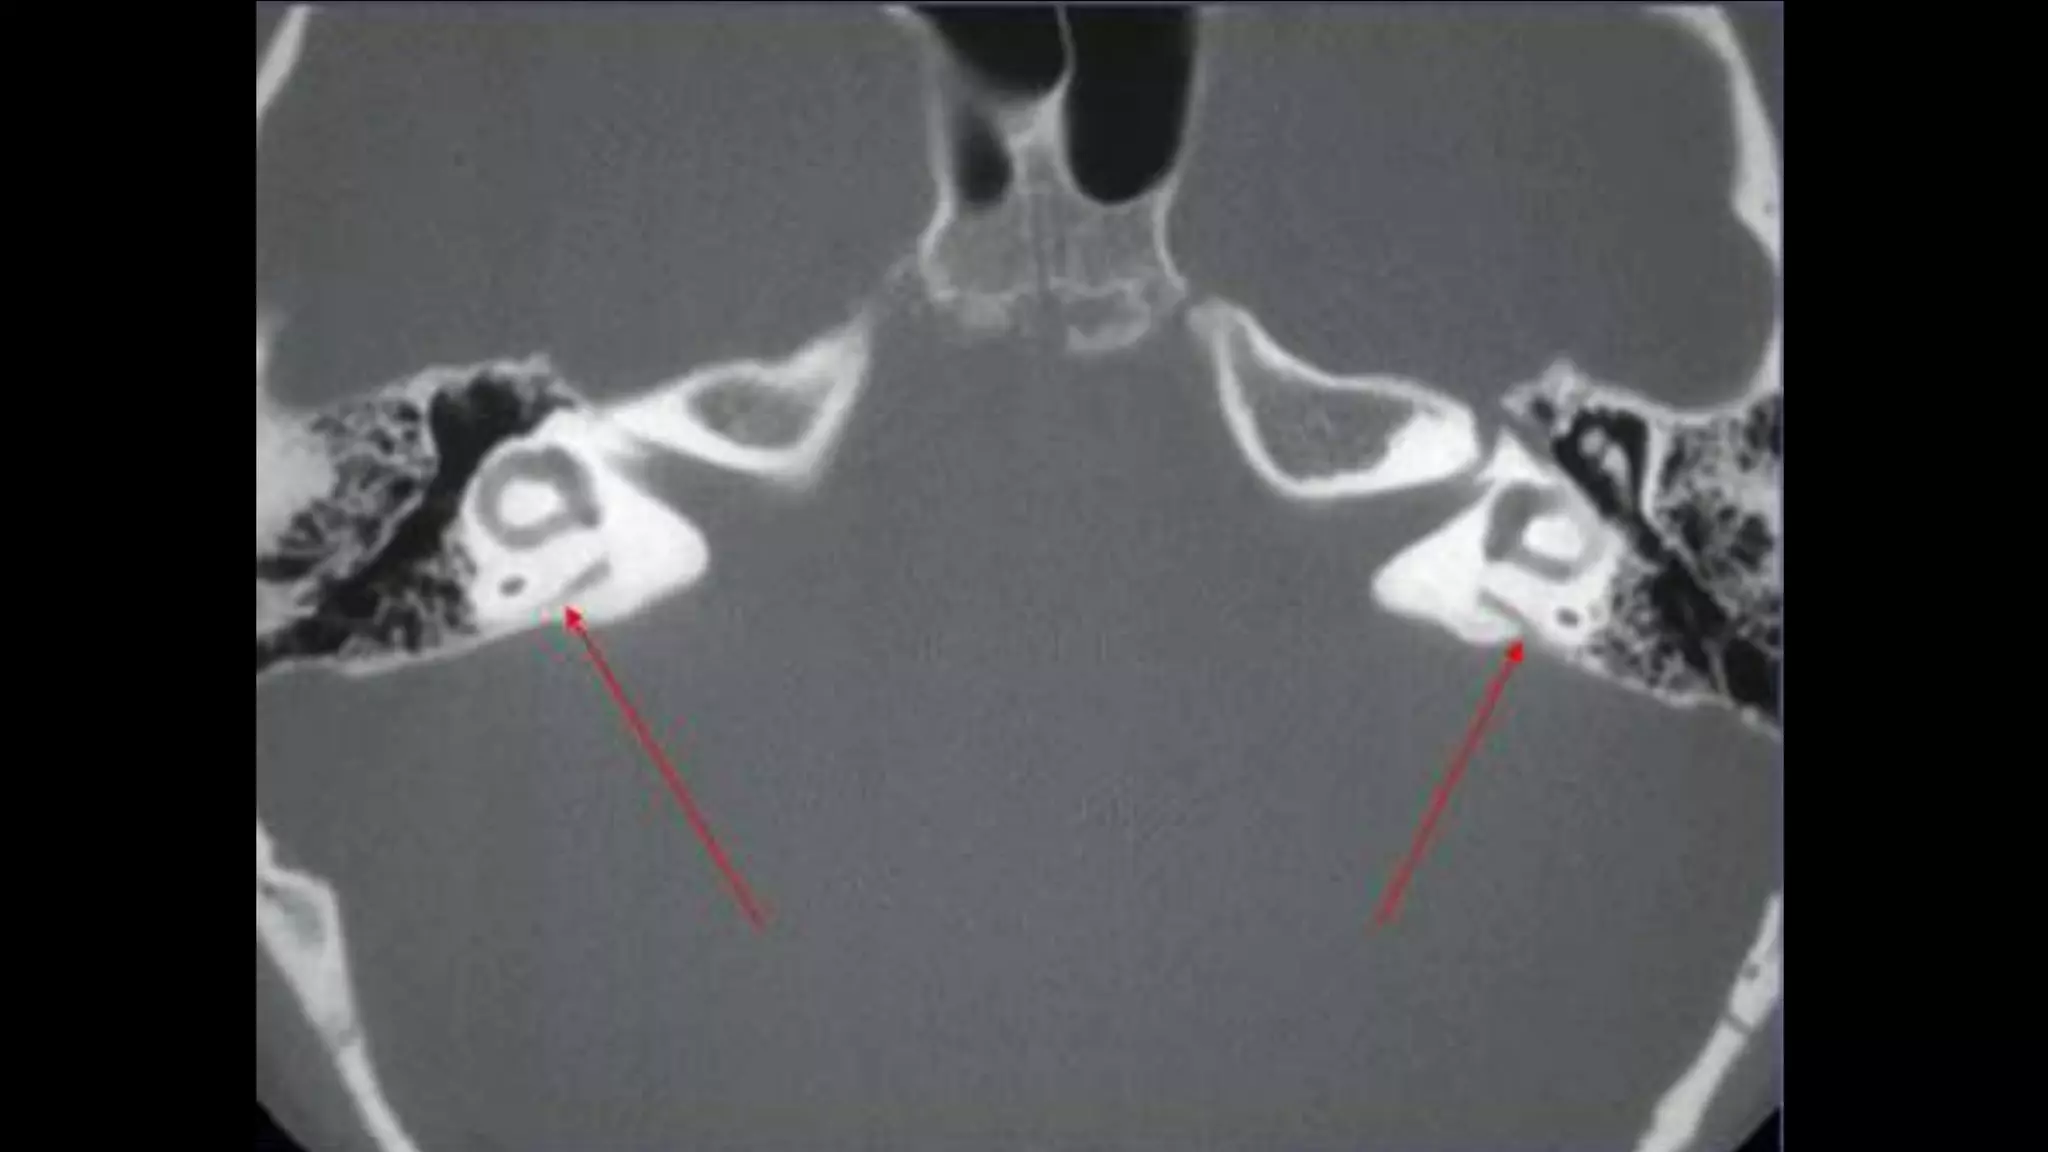

CORONAL

Middle Ear

• Three compartments in coronal

plane.

• A line drawn from lower edge of

the scutum to the tympanic

portion of the facial nerve -

epi/mesotympanum.

• parallel to the floor of the

external auditory canal

meso/hypotympanum